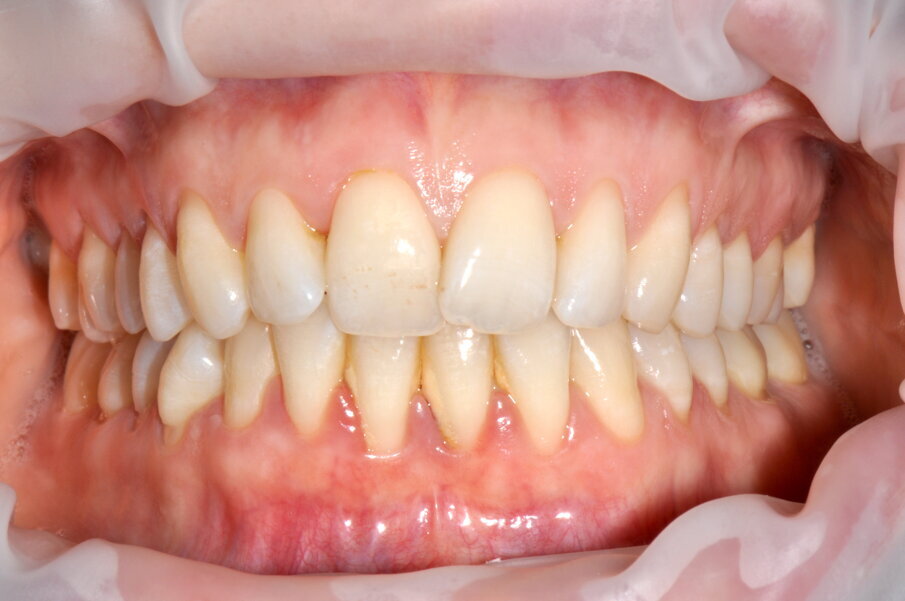

Paziente di sesso femminile di anni 27 con anamnesi generale negativa e senza storia di malattia parodontale, si presenta in prima visita lamentando sanguinamento gengivale durante le normali procedure di igiene orale domiciliare.

Viene quindi raccolta la documentazione fotografica ed effettuato lo screening PSR (Periodontal Screening and Recording), con risultato associabile a gengivite generalizzata (valore 1 e 2 per tutti i sestanti sia superiori che inferiori), con presenza di abbondanti depositi di placca e tartaro.

All’esame orale si evidenziano depositi di tartaro, in particolare nel quinto sestante nella zona linguale, e depositi di placca generalizzati (IP=2). I sondaggi parodontali risultano essere fisiologici con presenza di sanguinamento marginale e al sondaggio.

Figg. 1a-1c - Applicazione del rilevatore di placca che verrà usato come guida durante la terapia, nel versante vestibolare (1a), palatale (1b) e linguale (1c). Si noti lo scarso livello di igiene orale domiciliare e l’assenza di utilizzo dei presidi interdentali.